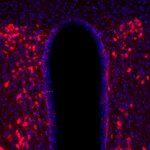

IHC: 1 : 500 gallery

IHC-P: 1 : 500 up to 1 : 750 gallery

Specificity The antibody recognizes Oxytocin. It may crossreact with the unprocessed precursor protein. K.O. validated PubMed: 37164226

Neuropharmacology (2023) 235: 109576. 408 004 IHC; KO verified; tested species: mouse